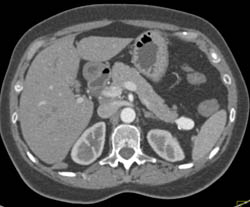

Splenic Cyst